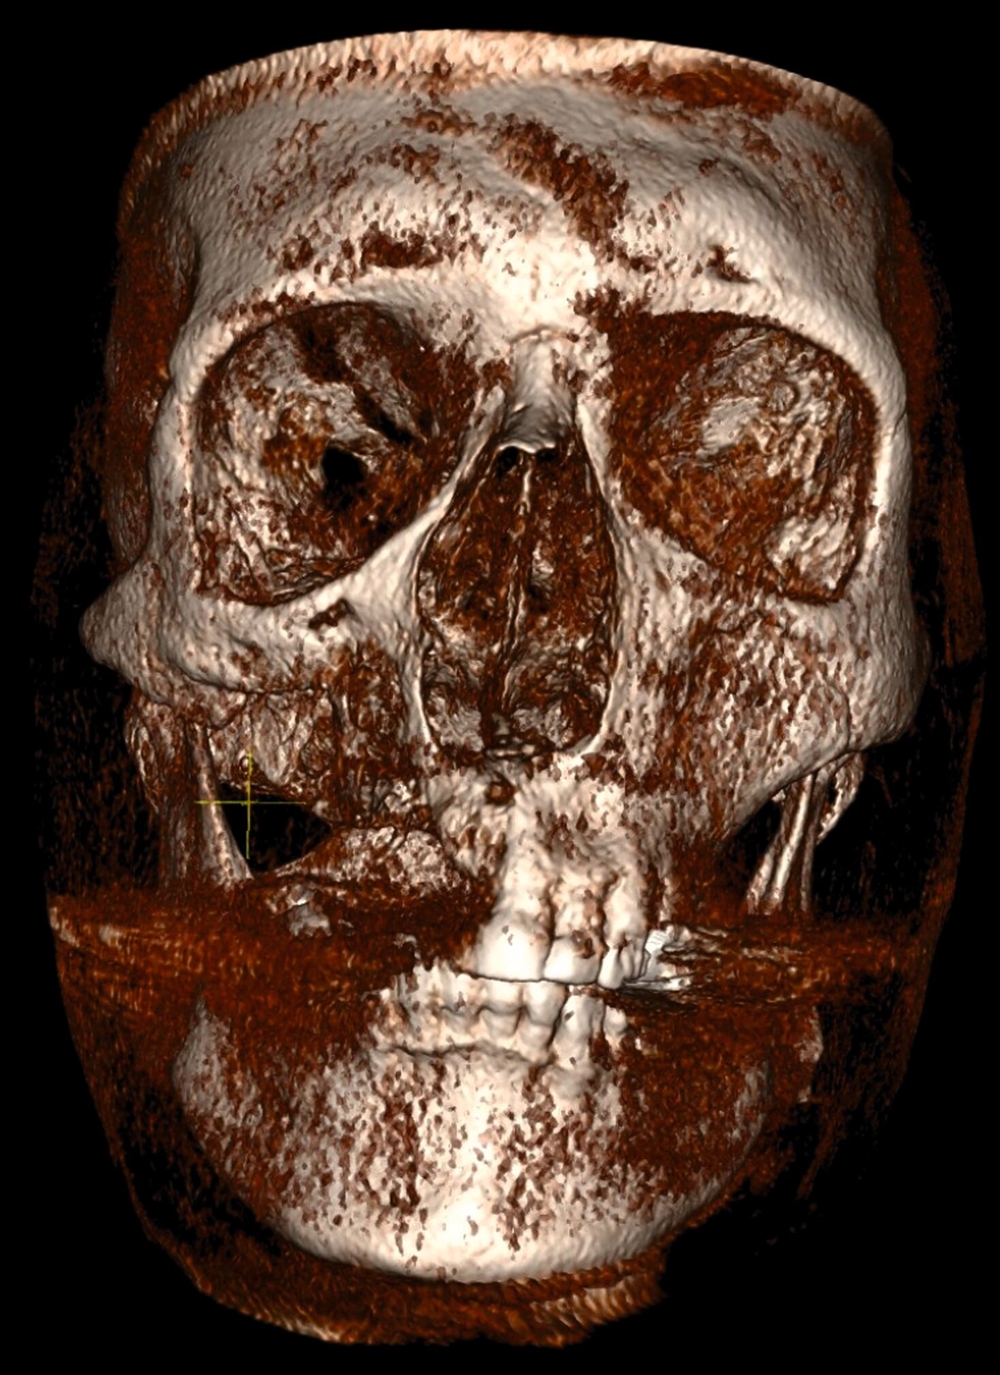

Die Erstbeschreibung von Zygoma-Implantaten — also von langen Implantaten, die ins Jochbein inseriert werden — stammt aus den 1980er-Jahren. Hier wurden sie bei Patienten nach Maxillektomien zur Wiederherstellung von Funktion und Ästhetik eingesetzt (Abbildungen 1 und 2).

Zu Beginn der 2000er-Jahre setzten Bedrossian und Chow et al. Zygoma-Implantate zur Sofortbelastung erfolgreich ein und wiesen ausführlich auf die Vorteile für die betroffenen Patienten im Vergleich zu herkömmlichen Verfahren im Sinne einer Augmentation und anschließenden Implantatinsertion hin [Bedrossian et al., 2006; Chow et al., 2006]. Später wurde der klassische Zugang zum sogenannten „Quad-Ansatz“ weiter modifiziert. In diesem Kontext ist der Oberkiefer derart atrophiert, dass weder im anterioren noch im posterioren Bereich ausreichend Knochen für die Platzierung herkömmlicher Zahnimplantate vorliegt. Daher werden jeweils zwei Zygoma-Implantate pro Seite ins Jochbein inseriert [Davo und David, 2019] (Abbildung 3). Unter Verwendung dieser Technik wurde in der Literatur eine Überlebensrate der Implantate von 98 Prozent berechnet [Varghese et al., 2021].